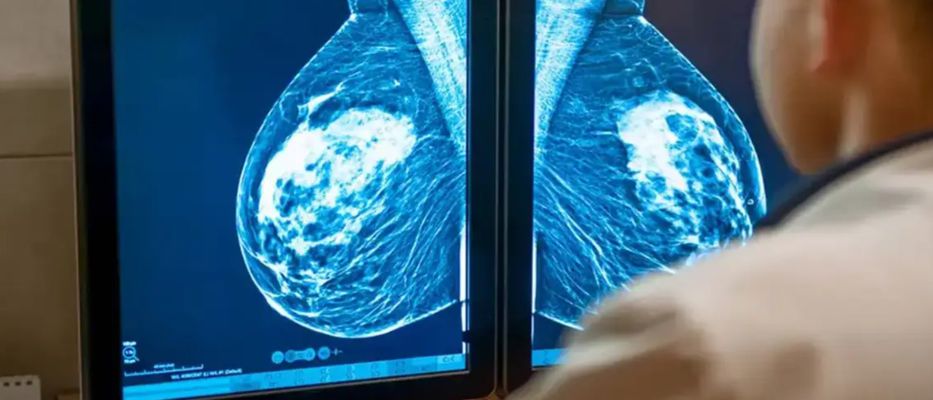

La investigación, difundida en la revista The Lancet Digital Health, analiza una herramienta denominada BRAIx, que utiliza algoritmos de aprendizaje profundo para examinar imágenes mamográficas y calcular una puntuación individual de riesgo en los años posteriores al examen.

A partir de las mamografías, los investigadores calcularon el llamado índice de riesgo BRAIx, que estima la probabilidad de desarrollar cáncer en el momento del cribado o en los cuatro años siguientes.